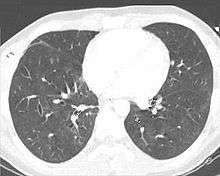

| A CT scan showing a pulmonary contusion (red arrow) accompanied by a rib fracture (blue arrow) | |

Computed tomography (CT scanning) is a more sensitive test for pulmonary contusion,[6][33] and it can identify abdominal, chest, or other injuries that accompany the contusion.[38] In one study, chest X-ray detected pulmonary contusions in 16.3% of people with serious blunt trauma, while CT detected them in 31.2% of the same people.[45] Unlike X-ray, CT scanning can detect the contusion almost immediately after the injury.[43] However, in both X-ray and CT a contusion may become more visible over the first 24–48 hours after trauma as bleeding and edema into lung tissues progress.[46] CT scanning also helps determine the size of a contusion, which is useful in determining whether a patient needs mechanical ventilation; a larger volume of contused lung on CT scan is associated with an increased likelihood that ventilation will be needed.[43] CT scans also help differentiate between contusion and pulmonary hematoma, which may be difficult to tell apart otherwise.[47] However, pulmonary contusions that are visible on CT but not chest X-ray are usually not severe enough to affect outcome or treatment.[37]